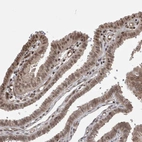

Immunohistochemical staining of human fallopian tube shows nuclear positivity in glandular cells.